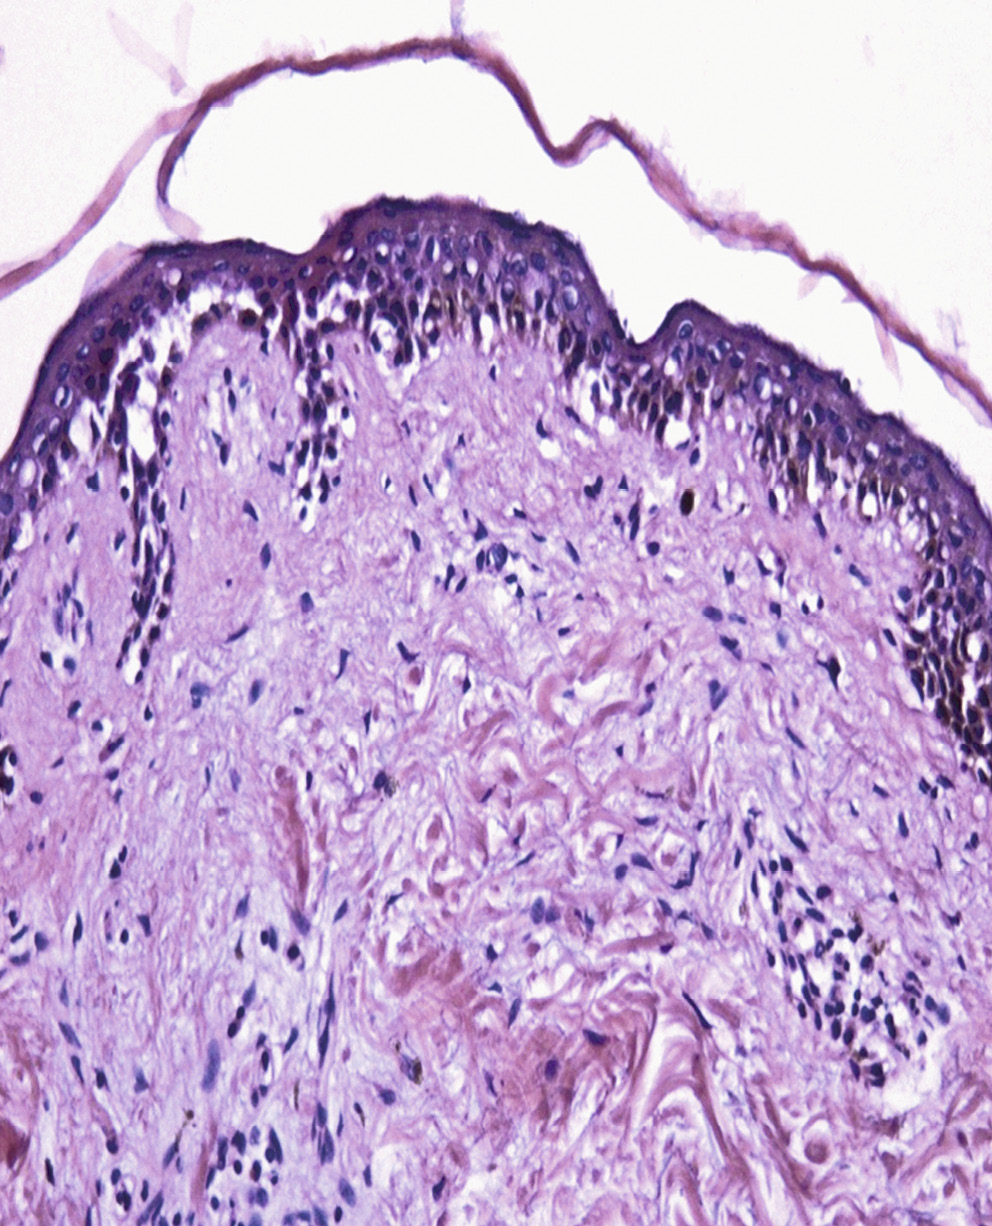

Проведено морфологическое исследование биоптата кожи, полученного в области свежего пузырного элемента. На всем протяжении эпидермиса отмечено очаговое формирование супрабазальных полостей или крупных щелей, в просветах которых — акантолитические клетки, фибрин, лейкоциты. Дерма отечна, периваскулярно — лимфоцитарные инфильтраты с примесью эозинофилов. Выявленные изменения характерны для вульгарной пузырчатки (рис. 2).

Рис. 2. IgG/IgA-пузырчатка. Морфологическое исследование биоптата кожи из очага поражения. Изменения, характерные для вульгарной пузырчатки. Выраженный надбазальный акантолиз с формированием крупных супрабазальных щелей; акантолитические клетки; лимфоцитарные инфильтраты в дерме. Окраска гематоксилином и эозином, × 100

Fig. 2. IgG / IgA pemphigus. Morphological study of skin biopsy from the lesion. Changes are featuring pemphigus vulgaris. Hyper supra-basal acantholysis with the formation of large suprabasal fissures; acantholytic cells; lymphocytic infiltrates in the dermis. Hematoxylin and eosin stain, × 100

При морфологическом исследовании биоптата кожи из очага поражения у больных IgG/IgA-пузырчаткой в большинстве случаев выявляются признаки акантолиза [6, 22]. У нашей пациентки были выявлены морфологические признаки пузырчатки в виде супрабазальных полостей и крупных щелей, в просвете которых находились акантолитические клетки. При исследовании биоптата кожи из очага эритемы признаки акантолиза могут быть крайне незначительны или отсутствовать, могут обнаруживаться нейтрофильные микроабсцессы в сосочках дермы, а у больных с пустулезными высыпаниями — пустулы в роговом слое и субкорнеальной локализации [6, 12, 29]. Характерен выраженный клеточный инфильтрат, содержащий большое количество нейтрофилов в эпидермисе и подлежащей дерме. Нейтрофилы в эпидермисе обнаруживались у 73% больных IgG/IgA-пузырчаткой [22]. Преимущественно нейтрофильный характер инфильтрата в коже больных IgG/IgA-пузырчаткой обусловлен наличием на моноцитах и гранулоцитах специфических связывающих участков для IgA-Fc-рецептора [31]. В ряде случаев в очагах поражения кожи у больных IgG/IgA-пузырчаткой в составе инфильтрата преобладали лимфоциты [32]. Отмечалось также присутствие в инфильтрате эозинофилов [15, 17]. Описан больной, у которого в эпидермисе обнаруживались клетки с признаками дискератоза [29]. У нашей пациентки при морфологическом исследовании биоптата кожи был выявлен лимфоцитарный инфильтрат с примесью эозинофилов.